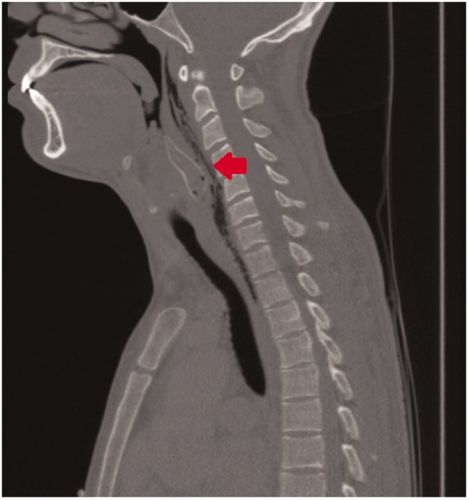

Спустя пару часов, когда все кустарные методы были испробованы, друзья отвезли шутника в ближайшую клинику. Странный пациент не захотел объяснить врачам, в чем причина его бедственного положения и просто жаловался на то, что подавился пищей. Но рентген сразу же показал, что внутри парня находится рыбка и пришлось признаться в исполнении дурацкого трюка.

Врачам удалось извлечь мертвую рыбку из горла пациента, после чего ему был назначен недельный курс антибиотиков. Парень отправился домой, а останки бедного сомика — в музей естественной истории города Роттердам, где их могут увидеть все желающие.

Почему возникла эта ситуация, едва не стоившая молодому мужчине жизни? Оказывается, безобидные с виду золотистые сомики (бронзовые коридорасы), в естественной среде обитания, имеют среди хищников плохую репутацию. За плавниками этих рыбок находятся острые твердые шипы, которые они, в случае опасности, поднимают торчком. В идеале это должно помешать крупной рыбе проглотить малыша. Но человек устроен несколько иначе и шипы задержали сомика там, где ни он сам, ни его жертва уже ничего предпринять не могли.